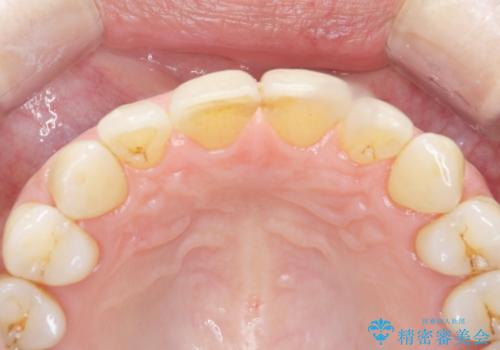

- 歯ぎしりが気になる 歯が将来ダメになるのが怖いとの事で相談を受けた患者様です。

型取り(上下)をして自費のナイトガードを作製しました。